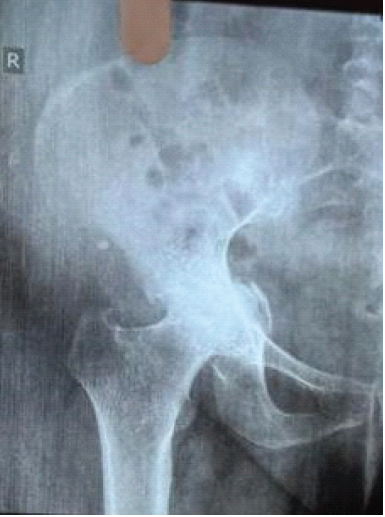

Total Hip Arthroplasty in a Case of Neglected Central Hip Dislocation with Isolated Quadrilateral Plate Fracture: A Case Report with Review of Literature

Somok Banerjee , Santu Sarkar , Alok Chandra Agrawal , Harshal Sakale , Suhas Mahendrakar , Devashish Singh

………………………………p.137-141